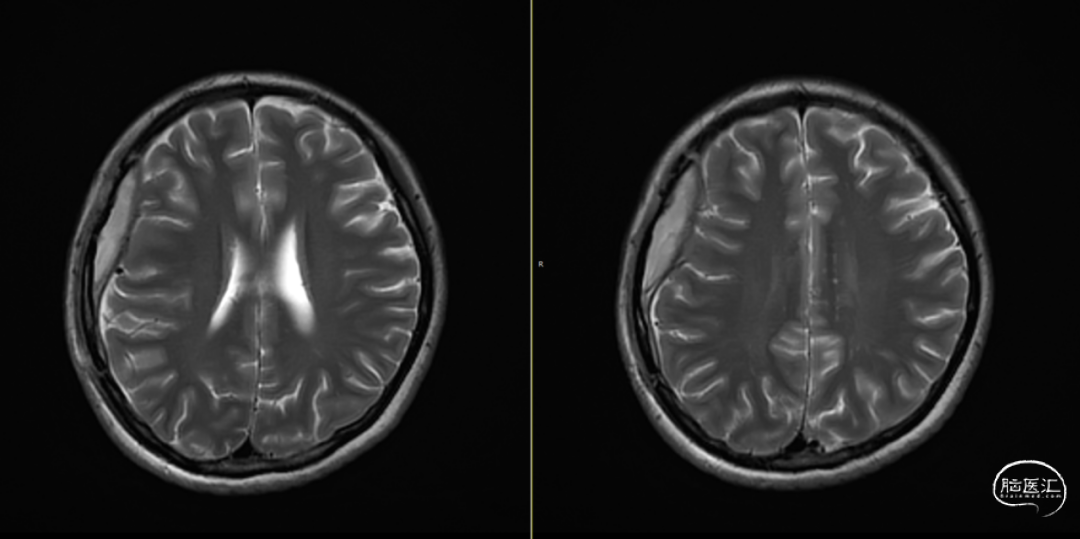

术后第1天颅脑CT复查(如上图)

术后58天颅脑磁共振平扫(如上图):右侧额顶颞部见斑片状异常信号,呈片状T1WI低、T2WI稍高信号影,T2FLAIR呈稍高信号,边界清,右侧额顶颞叶脑组织受压,DWI(b=1000)呈混杂高信号,相应ADC呈混杂高信号影。